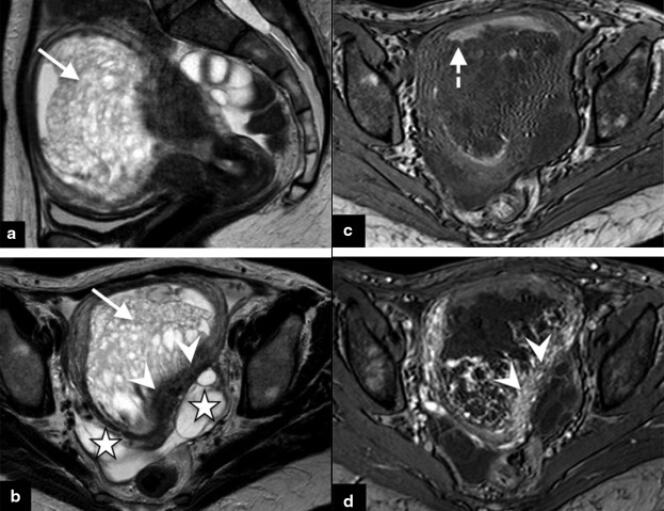

IRM pelvienne mettant en évidence une môle invasive chez une patiente de 40 ans présentant des hémorragies de l’utérus. PIERRE-ADRIEN BOLZE Ce sont des tumeurs féminines méconnues,d’autant plus cruelles qu’elles surviennent à l’occasion de l’attente d’un « heureux événement ». Chez près d’une femme enceinte sur mille en Occident (et près d’une sur cent en Asie),en effet,une masse tumorale se développe à partir du placenta,cet organe essentiel qui assure les échanges entre le sang de la mère et celui de l’embryon.

Lors de ces grossesses pathologiques,des lésions précancéreuses,nommées « môles hydatiformes »,se développent à partir d’une couche de cellules,le trophoblaste,qui,en temps normal,entoure l’embryon et forme de nombreuses villosités qui ancrent le placenta dans l’utérus.